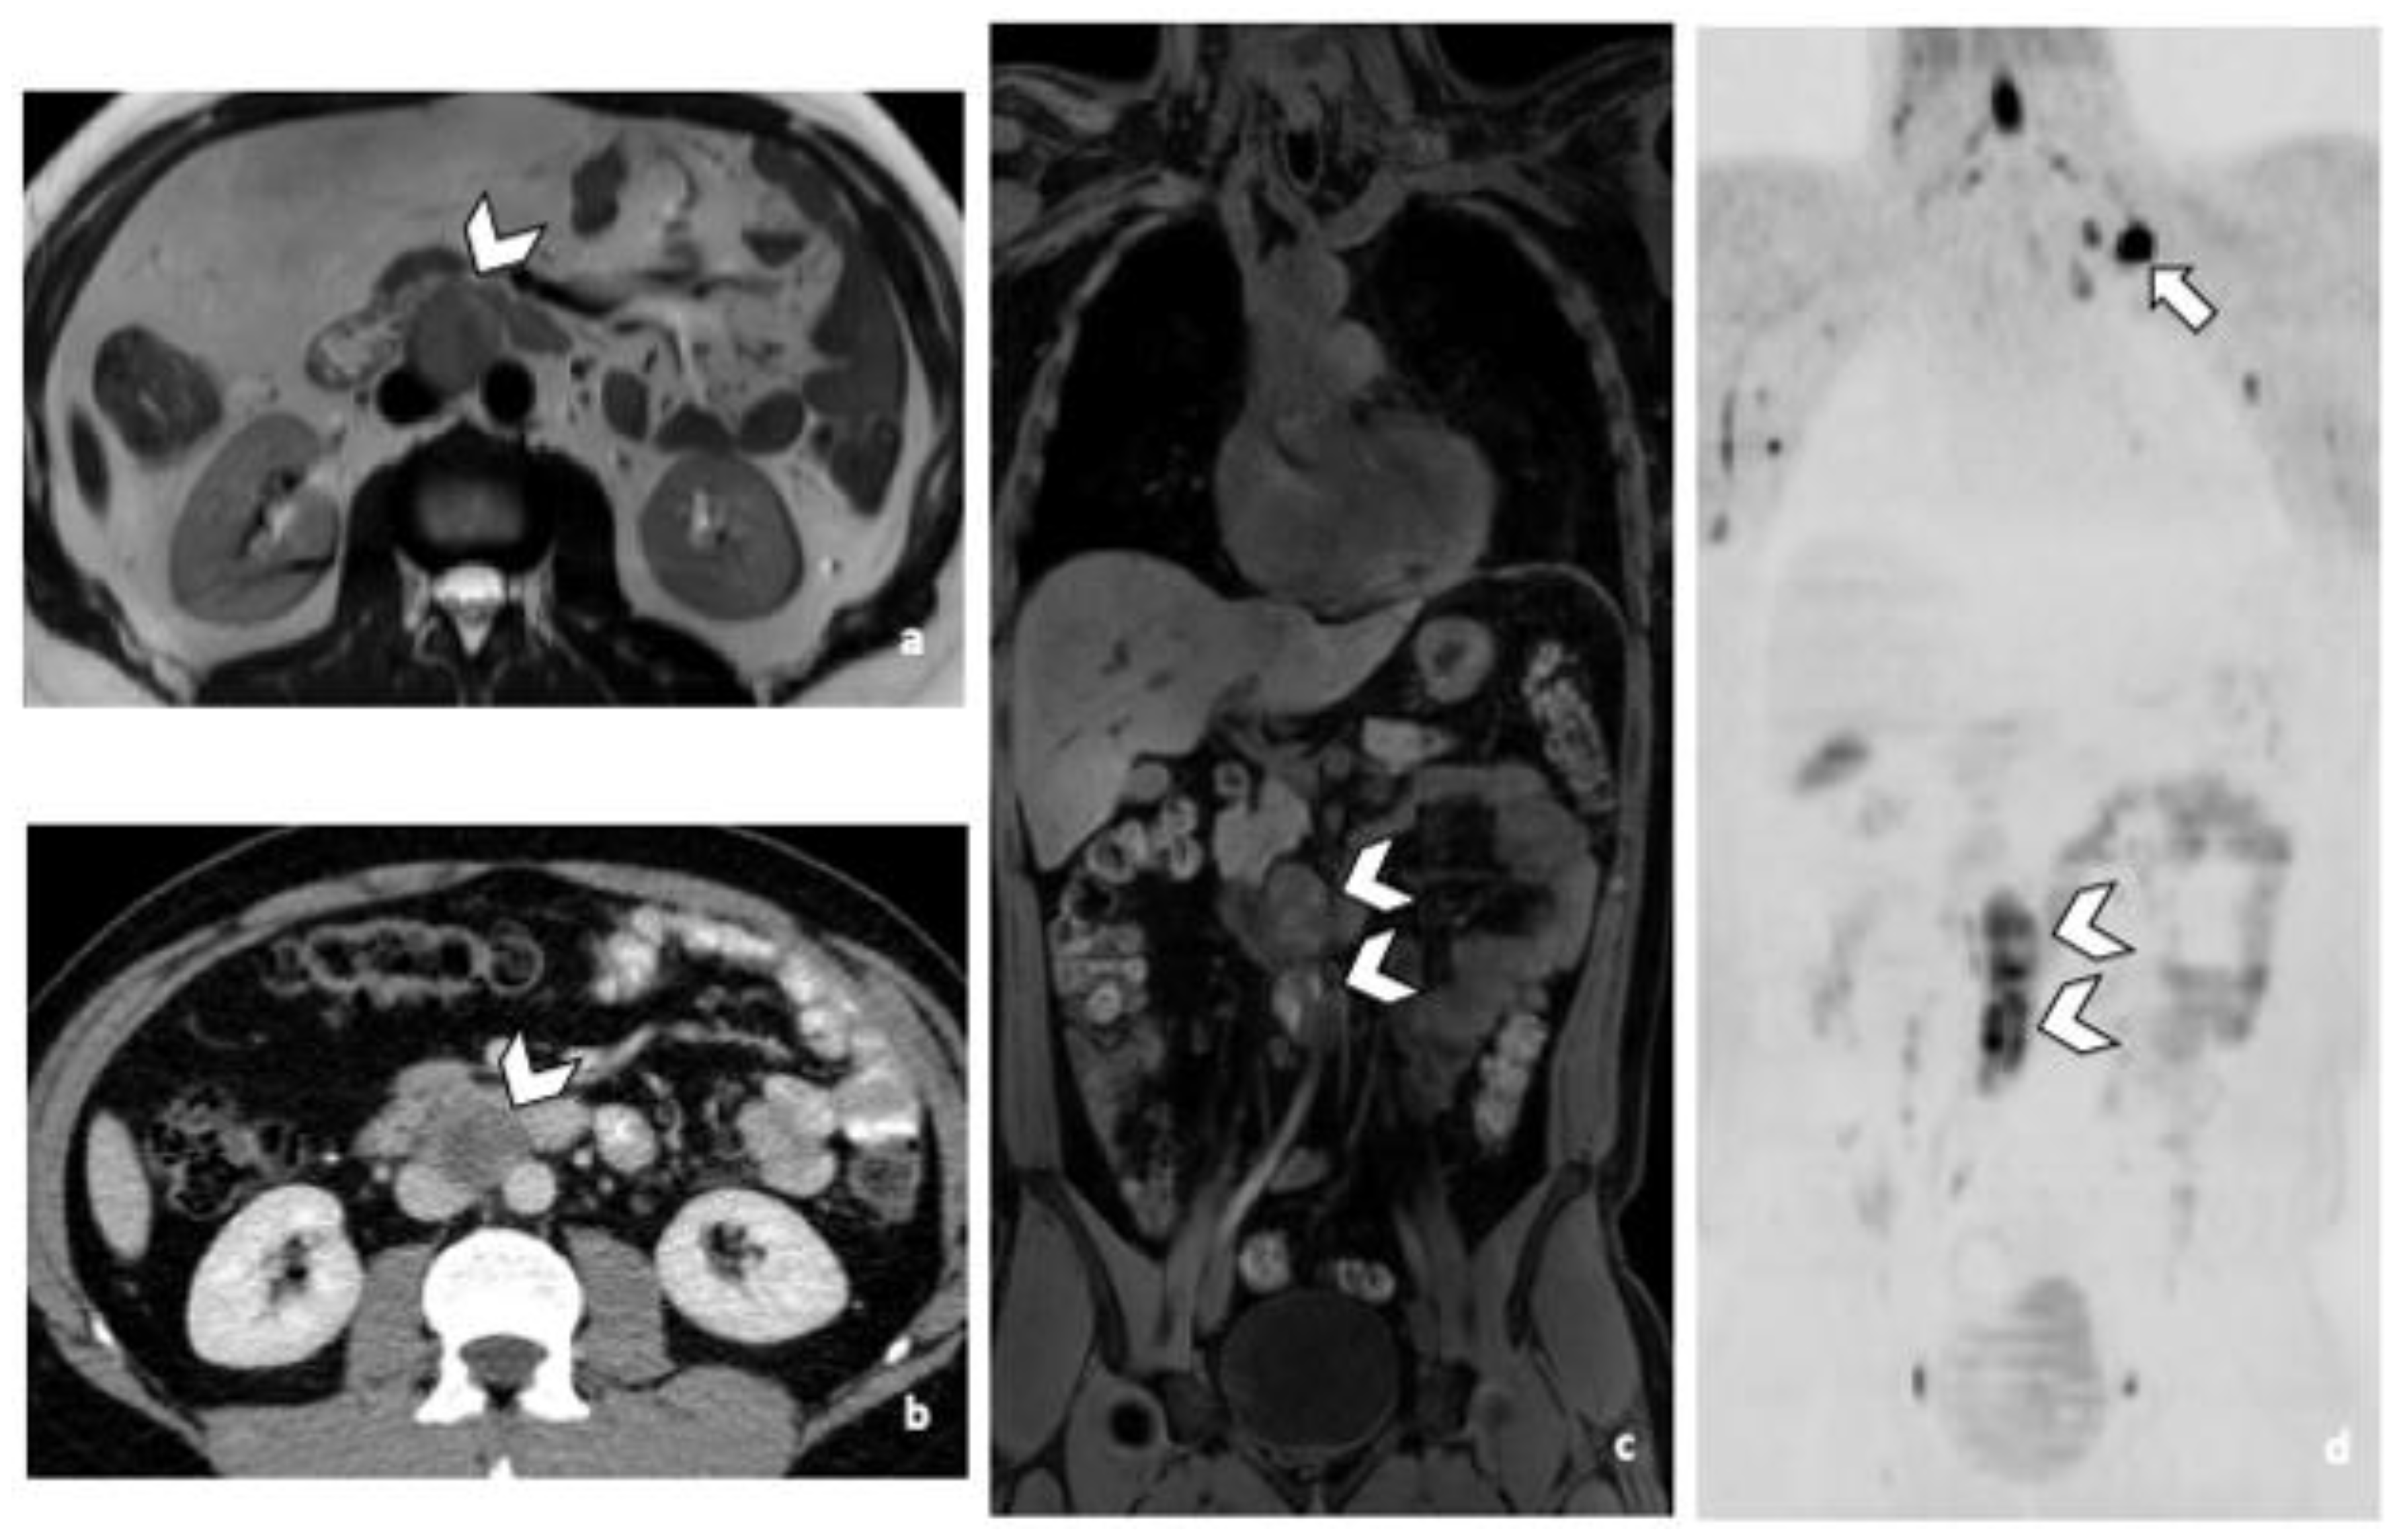

Figure 1.

29-year-old man with NSGCC. Axial T2-weighted MR image (a), coronal reformatted 3D T1 GRE Fat-Sat (c) and high b-value DWI (inverted greyscale, b = 1000 s/mm2) (d) of MR images of the whole body and axial CT image after intravenous injection of iodinated contrast agent (Xenetix 350®) and per os contrast opacification (Telebrix Gastro® 5%) (b), showing interaorticocaval enlarged pathological lymph nodes (arrowheads), identified by both readers during MRI and CT readings. The lymphadenopathies show an intermediate to high signal intensity on T2 (a), an heterogenous low and high signal intensity on T1 (c) compatible with histological component of NSGCC and a restricted Diffusion (d). Note the presence of a left supraclavicular lymphadenopathy visible on DWI (d: arrow). Abbreviations: NSGCC: Non-Seminomatous Germ Cell Cancer, 3D: Three Dimensional, T1 GRE: T1 Gradient Echo, DWI: Diffusion Weighted Imaging, MRI: Magnetic Resonance Imaging, CT: Computed Tomography.